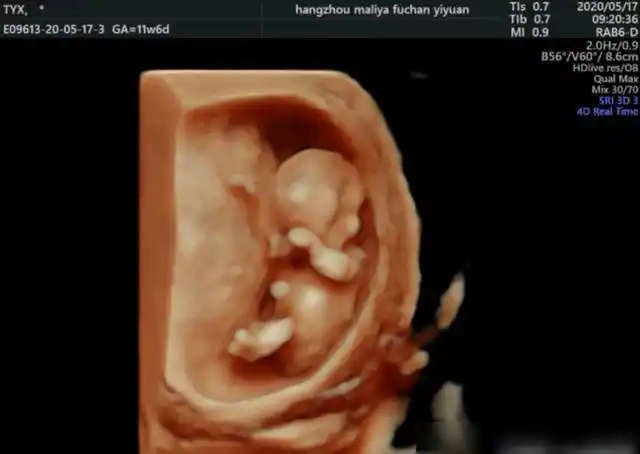

皮肤开始出现毛囊,肝脏开始活动头部占胎儿身长的一半外部生殖器官

孕 周二维超声示胎儿男性外生殖器,呈「郁金香征」